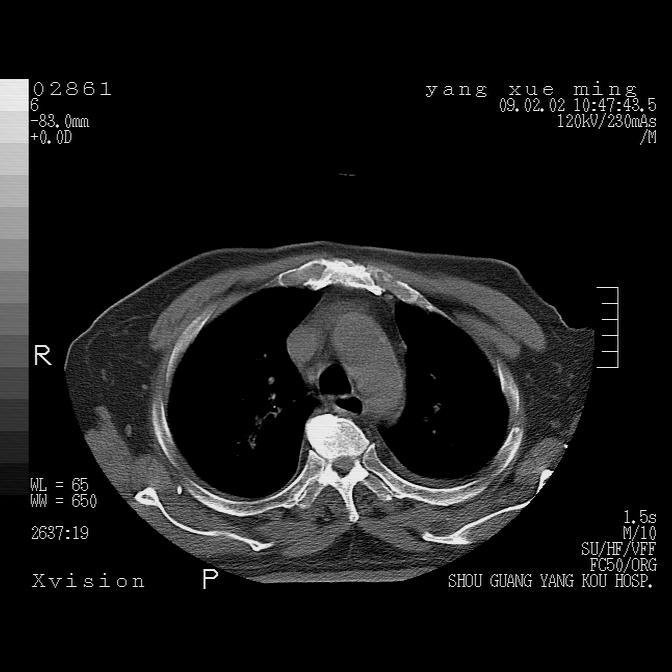

以下是引用zbp537在2009-2-3 19:08:00的发言:[br]我诊断为肺泡性肺水肿。[br]诊断依据:[br]1、心影普遍增大,肺血管增粗,并见絮状高密度影,肺门改变显著。[br]2、临床上表现胸闷咳嗽,无发烧,不是一个典型的肺部感染的病史。

以下是引用lkc8963在2009-2-3 20:11:00的发言:[br]1)右上肺陈旧病灶。2)右下肺团块及团片影,影像表现符合感染。3)左心增大,左冠脉钙化,符合冠心病。4)双侧肺门扩大,以左侧为著,肺动脉干略粗,左上肺局限性气肿,为谨慎起见,需除肿瘤,建议增强。

以下是引用lkc8963在2009-2-3 20:11:00的发言:[br]1)右上肺陈旧病灶.2)右下肺团块及团片影,影像表现符合感染.3)左心增大,左冠脉钙化,符合冠心病.4)双侧肺门扩大以左侧为著,肺动脉干略粗,左上肺局限性气肿,为谨慎起见,需除肿瘤,建议增强.